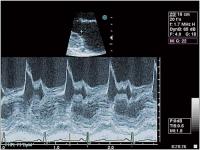

Abbildung 2: Sogenannter "diastolischer shudder" des vorderen Mitralsegels in der M-Mode-Registrierung (parasternal lange Achse)